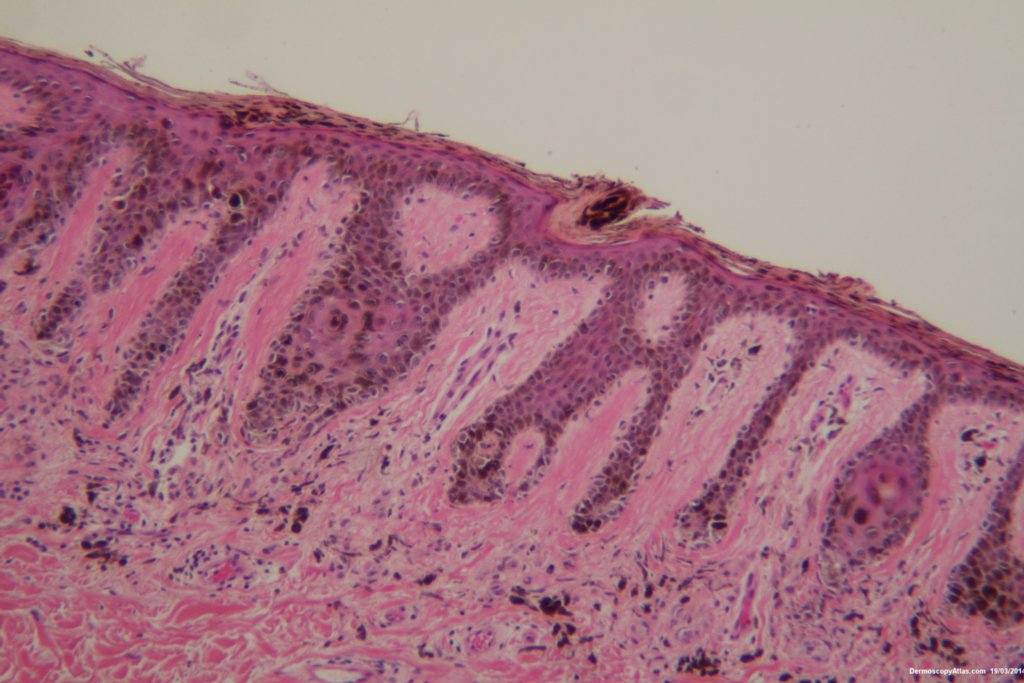

Diagnosis: Dysplastic Junctional Lentiginous Nevus

An elderly male asked about the pigmented lesion on his lower back. The dermatoscopy showed internal lines and dark clods with a central dark structureless area. Histology showed a dysplastic junctional lentiginous nevus.